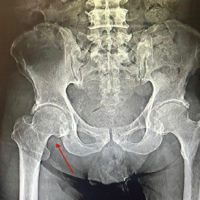

An 8-year-old female child presented with a 2-year history of a fixed elbow with almost no movement and a palpable bony mass. She had sustained significant trauma to her left elbow, followed by indigenous treatment in the form of native massage and slab for 2 months before the onset of symptoms [3]. Although it was her non-dominant limb, she had difficulties with daily activities such as clothing herself and tying shoelaces [4]. A clinical examination showed bony ankylosis and a fixed elbow with minimal range of movement at the elbow to be 0–10°. A palpable diffuse bony mass was present on the anterior aspect of the elbow, with the margins tapering to the corresponding muscles. No distal neurovascular compromise or limb length discrepancies were detected. Due to bone hyperplasia early during the disease, such masses may be mistaken for soft-tissue tumors or osteosarcomas. Soft-tissue tumors or osteosarcomas are often accompanied by periosteum hyperplasia, bone-cortex destruction, and unclear borders on X-ray radiography, which is not seen in this case. Thus, the mass was not a tumor (Fig. 1 and 2).